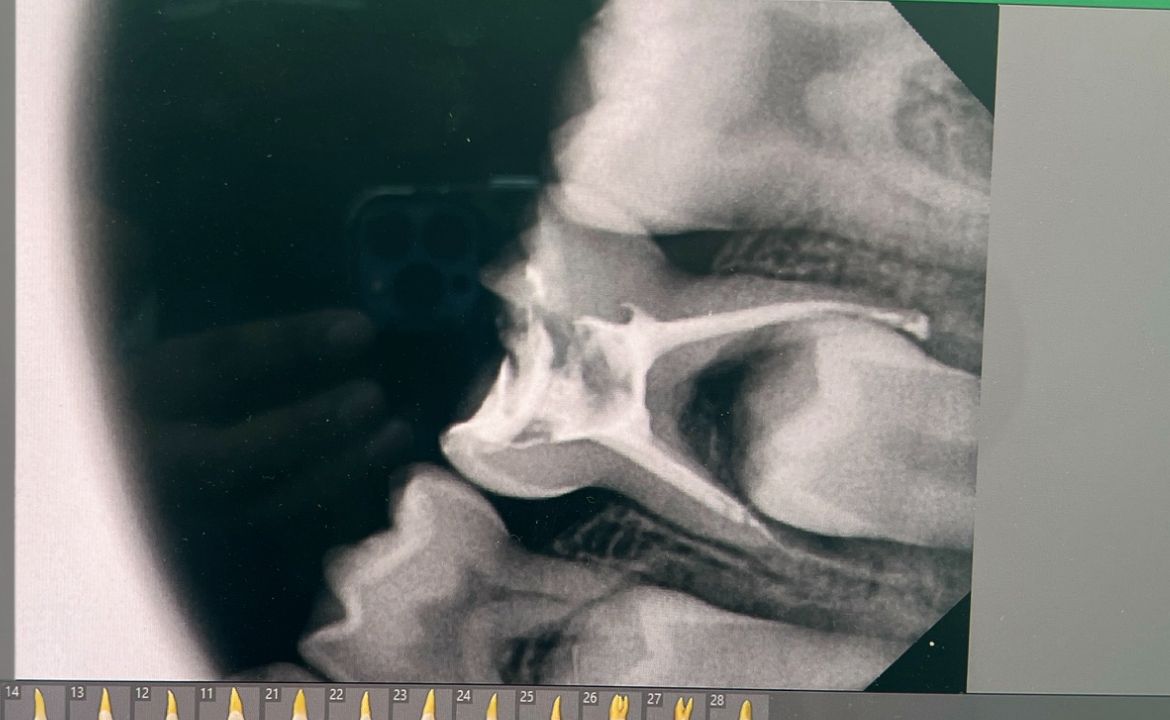

Pediatric Dentistry focuses on providing specialized dental care for infants, children, and teenagers in a safe, friendly, and comforting environment. This branch of dentistry aims to ensure healthy tooth development, prevent early childhood dental problems, and build positive dental habits from a young age. With gentle techniques, child-friendly communication, and preventive treatments, pediatric dentistry helps children maintain bright, healthy smiles while reducing dental anxiety and promoting long-term oral health.

Ensures healthy tooth and jaw development